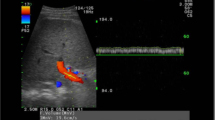

Although computed tomography (CT) and magnetic resonance imaging (MRI) can anatomically identify the development of collateral circulation, early portal hemodynamic changes cannot be assessed [13]. Doppler ultrasonography (US) remains the first choice for evaluating blood flow in the PV system. However, it has many limitations, including the inability to observe deep areas and many sites simultaneously, the narrow field-of-view (FOV), the possibility of different measurements depending on the angle, and poor interobserver reproducibility [14,15,16].

For the quantitative evaluation of 4D flow MRI, blood flow was analyzed using GTFlow (GyroTools LLC, Zurich, Switzerland). In addition to hemodynamic visualization, the same radiologists (A.H. and A.Y.) manually placed a region of interest in consensus on the cutting planes of the portal trunk (PT), RPV, LPV, superior mesenteric vein (SMV), and splenic vein (SV). To assess the accuracy of the placement of regions of interest on PCA images, we compared the area of PCA with that of contrast-enhanced MR angiography on portal phase images and found a significant correlation in all planes (Spearman’s ρ = 0.888 to 0.966, p < 0.001). Therefore, we manually set up regions of interest in the PCA images. Subsequently, the area (vessel diameter, mm2), forward flow (mL/s), backward flow (mL/s), net flow (mL/s; the difference between forward and backward flows), total flow (mL/s; the sum of forward and backward flows), and average velocity (cm/s) in each cross-section were calculated (Fig. 3). All vessel segmentation was performed manually without using a threshold. Quantitative values were calculated as averages of data obtained using time-varying (time-resolving) PCA, and the approximate analysis time was 5–10 min per case.

Velocity map of four-dimensional (4D) flow MRI of a 46-year-old female patient with normal liver (Fib-4 index = 0.39, APRI = 0.16). The 4D flow MRI velocity map shows the flow in the portal trunk (PT, dark blue), right portal vein (RPV, light blue), left portal vein (LPV, green), superior mesenteric vein (SMV, yellow), and splenic vein (SV, orange). For 4D blood flow analysis, the radiologists manually defined the region of interest on the PT, RPV, LPV, SMV, and SV cutting planes. Abbreviations: APRI aspartate aminotransferase-to-platelet ratio index, Fib-4 index fibrosis-4 index, MRI magnetic resonance imaging